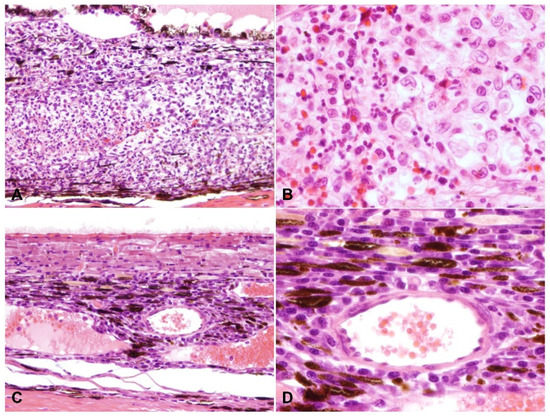

2.2. Ocular Lesions in Cats with FIP-induced Uveitis

2.3. Detection of Viral Antigen and RNA Via Immunohistochemistry, RNAscope® In Situ Hybridization and RT-qPCR

2.4. Relationship between Type of Inflammation and Detection of Viral Antigen and RNA via Immunohistochemistry, RNAscope® In Situ Hybridization and RT-qPCR